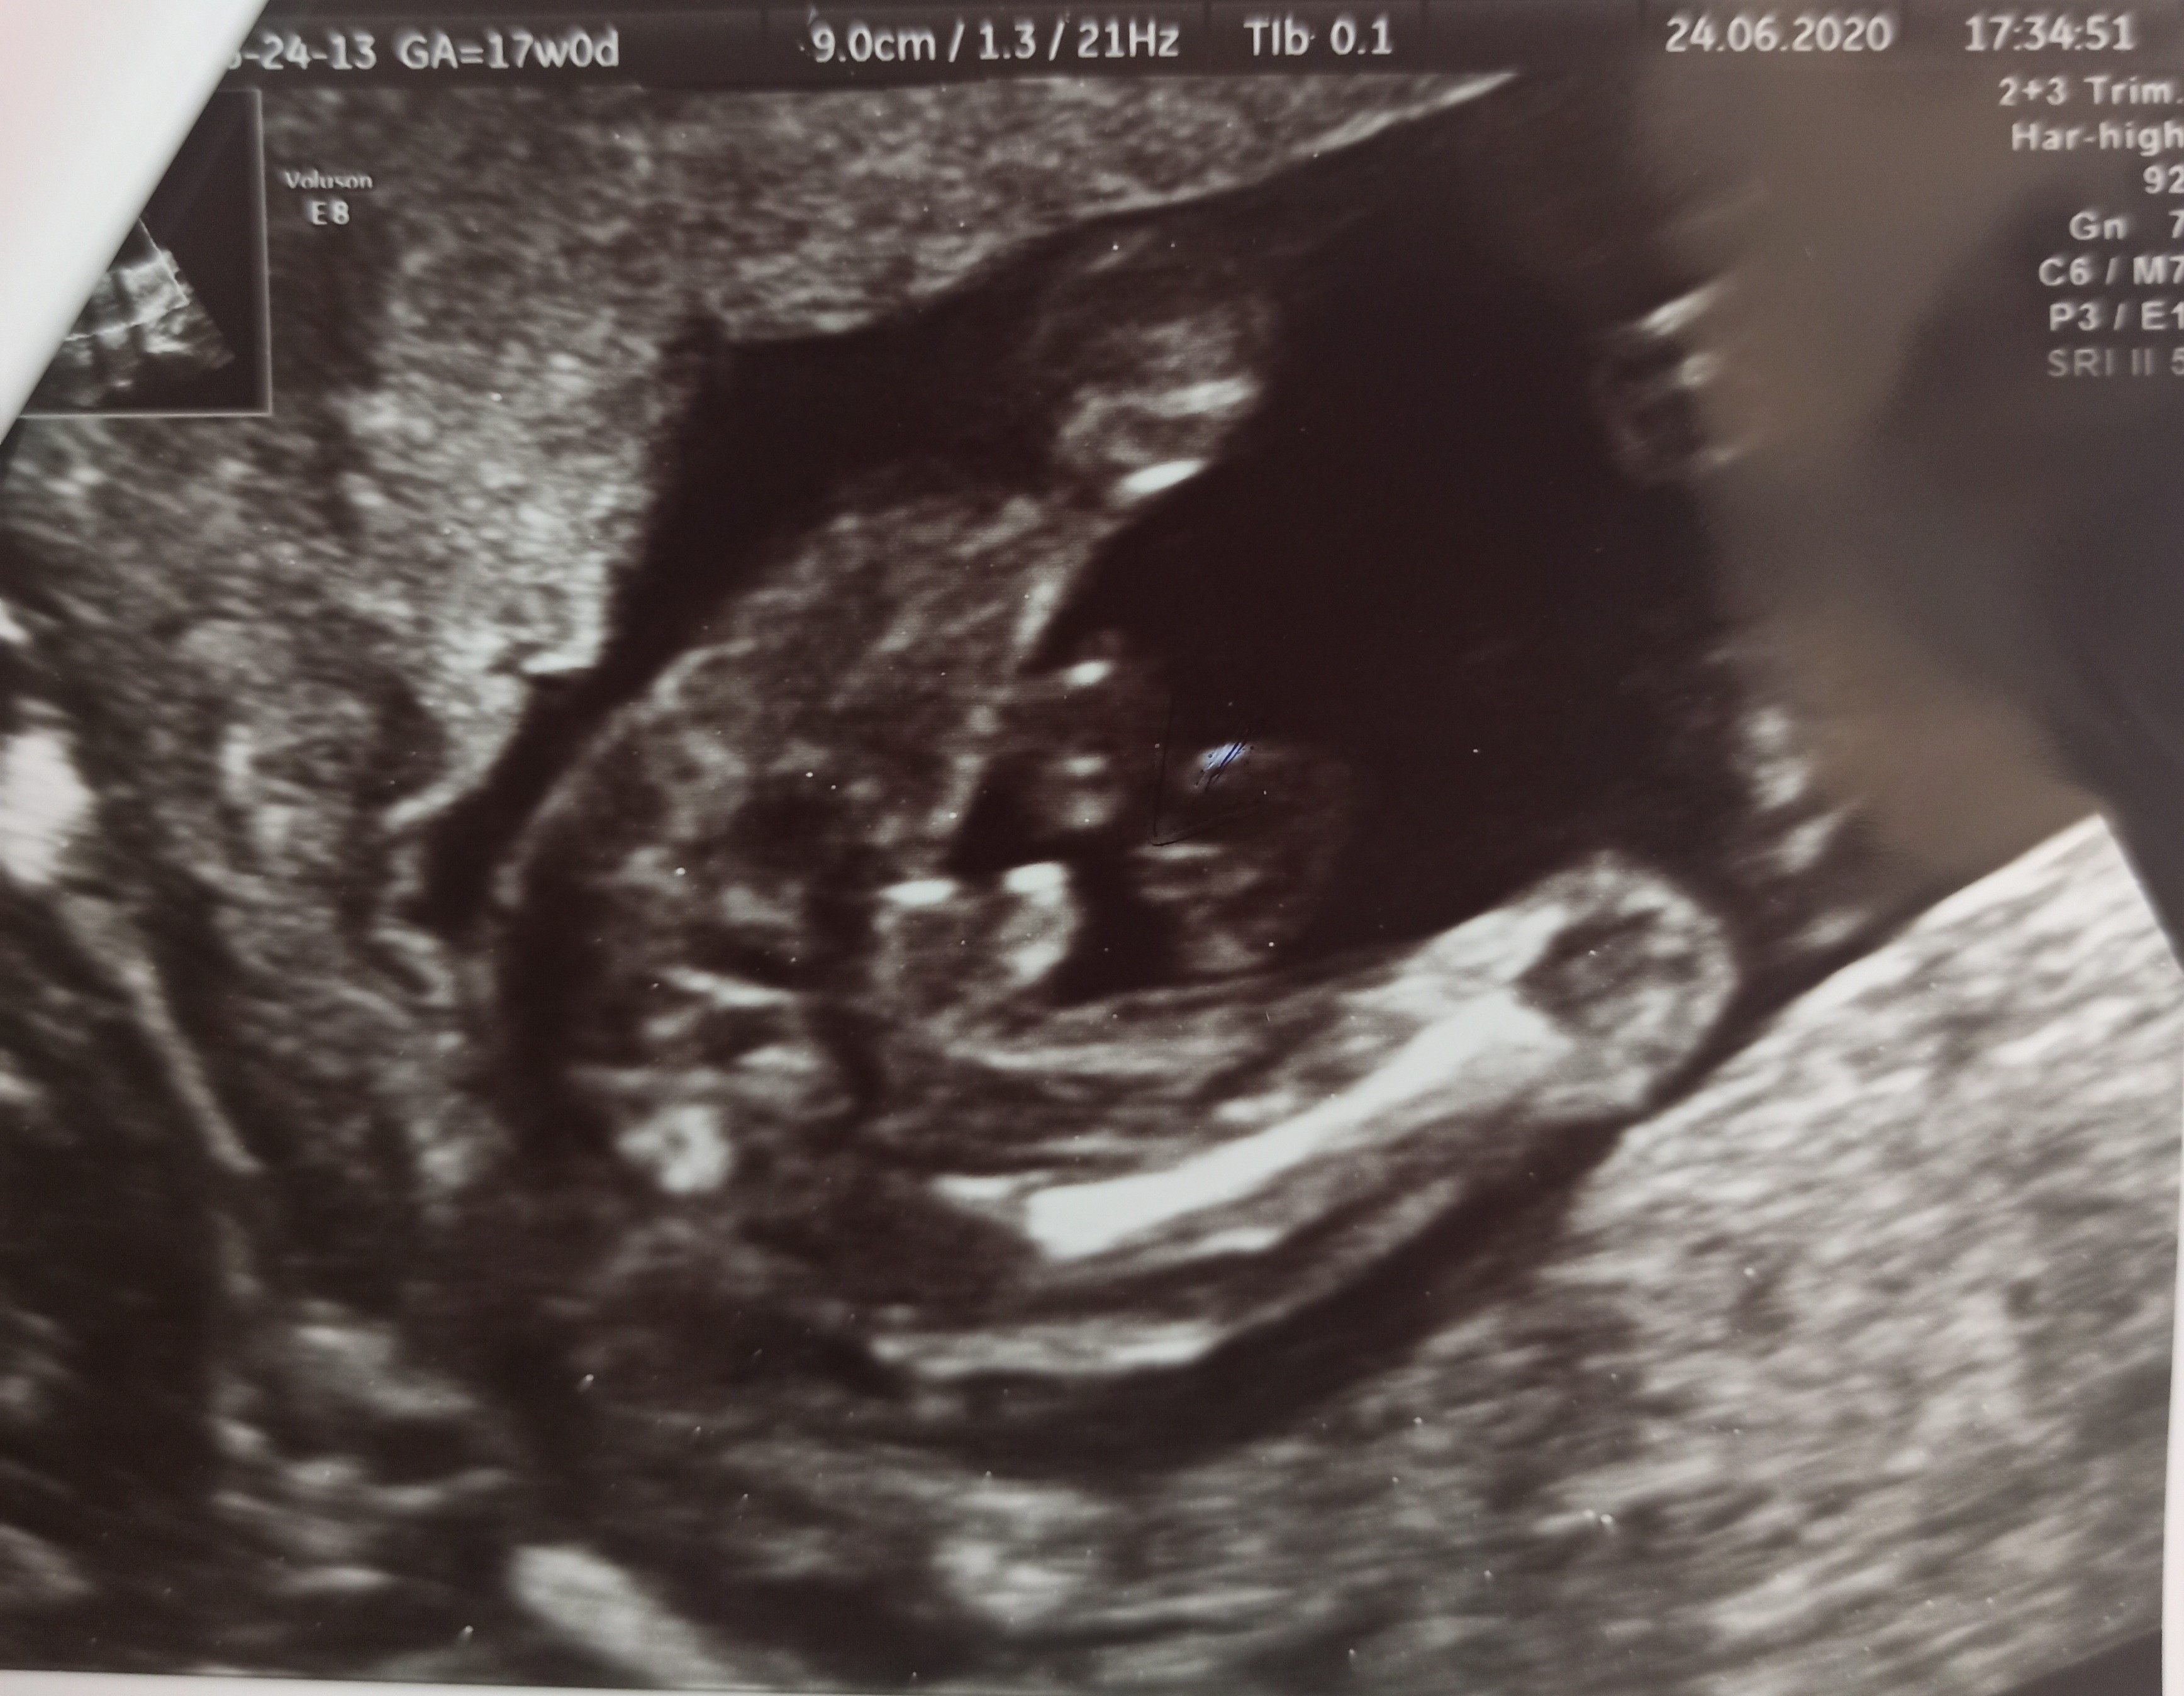

Witam w 19 tygodniu ciąży dowiedziałam się ze będę miała dziewczynkę w 20 tyg okazało się jednak , że to chłopak. Sama już nie wiem bo na jednym usg widać na pewno dziewuche a na drugim chłopca. Może to pempowina ?? Może ktoś mi pomoże rozwiązać ta zagadkę

Załączniki

• 4A8F5FF1-76CA-4DE0-AC12-5EDF08E820F2.jpg

4A8F5FF1-76CA-4DE0-AC12-5EDF08E820F2.jpg

596,4 KB · Wyświetleń: 44 137